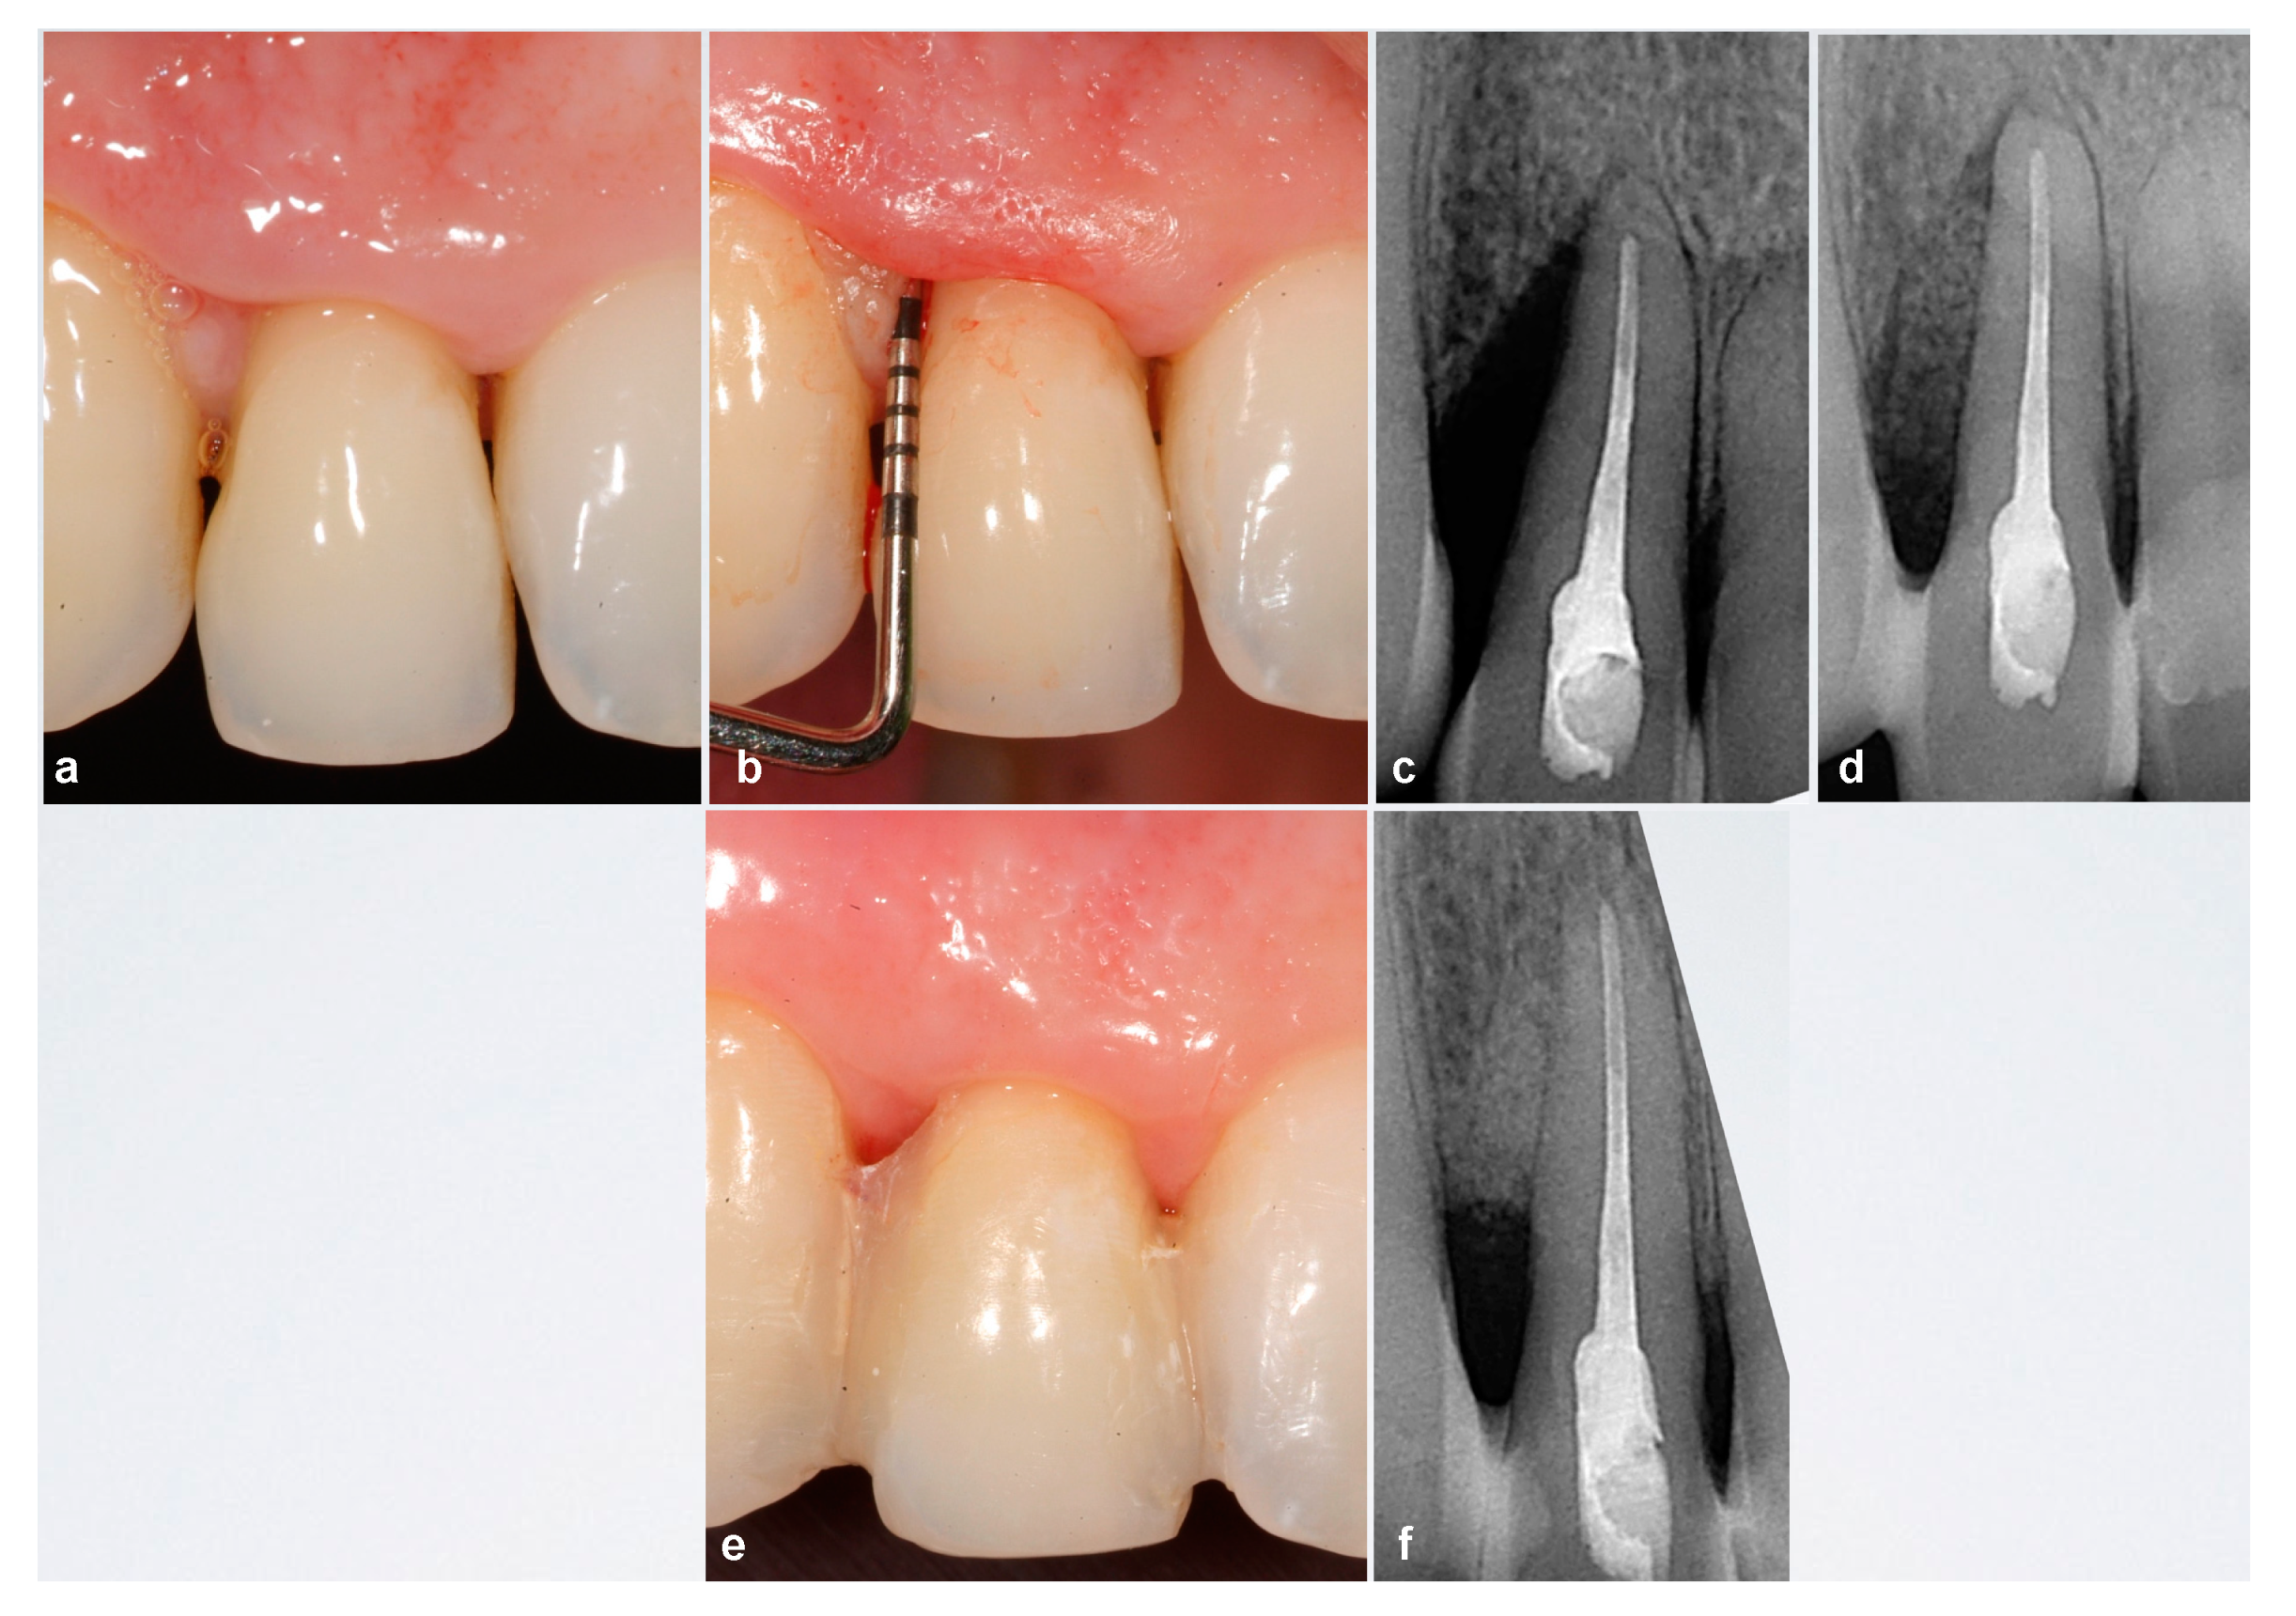

Interimplant Papilla Reconstruction in the Esthetic Zone。Interdental Papilla Reconstruction Surgery - Advanced。sddefault.jpg。「乳頭再建 = Papilla reconstruction」山口文誉 / 鈴木真名 / 髙橋雅仁定価: ¥ 14000裁断済みです。Dr.夏秋の臨床図鑑 虫と皮膚炎 改訂第2版。。書き込みはありません。#山口文誉 #鈴木真名 #髙橋雅仁 #本 #自然/医療・薬学・健康